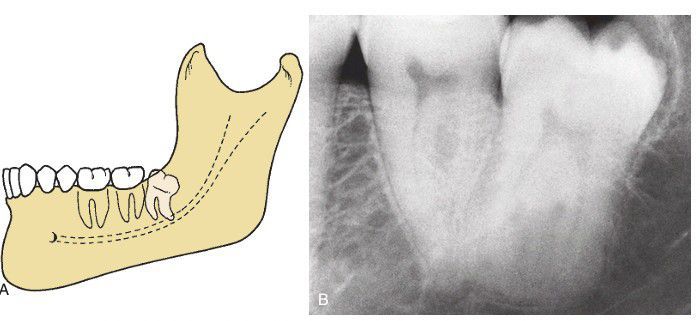

(A) Distoangular impaction—an uncommon and the most difficult of the four types of impactions to remove. (B) The occlusal surface of distoangular impaction is usually embedded in the ramus of the mandible and requires significant bone removal for extraction.